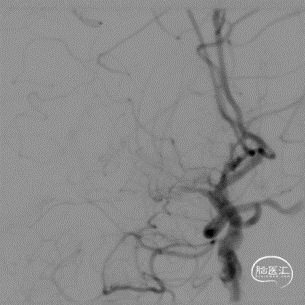

脑血管造影:右侧大脑中动脉M1段闭塞,代偿不足。

左椎动脉V4段重度狭窄。

微导丝辅助微导管通过闭塞段,以赛诺神畅Neuro LPS-1.5-15mm球囊分次扩张闭塞段。

球扩后造影见闭塞段恢复正向血流M1段远端夹层表现。